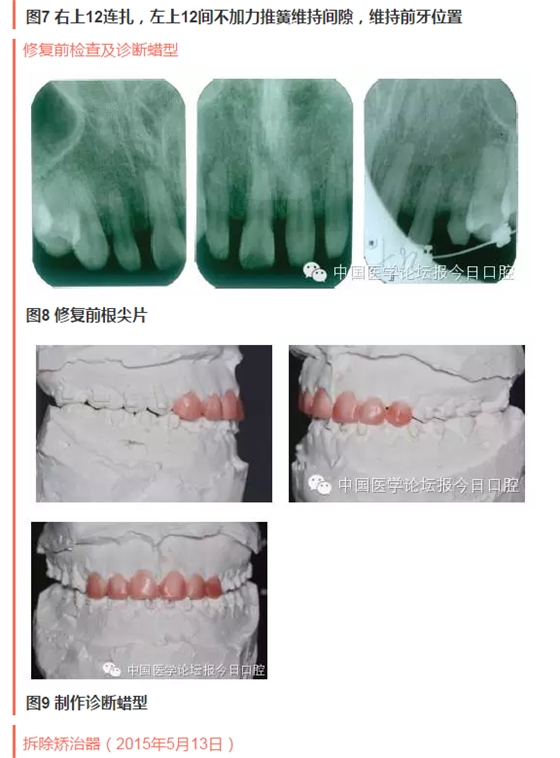

QQ圖片20150714135304.png

QQ圖片20150714135328.png

QQ圖片20150714135356.png

QQ圖片20150714135424.png

QQ圖片20150714135504.png

QQ圖片20150714135533.png